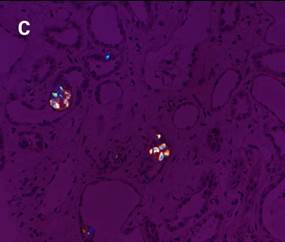

痛風(fēng)診斷金標(biāo)準(zhǔn)是針吸活檢發(fā)現(xiàn)尿酸鹽結(jié)晶,尿路感染、關(guān)節(jié)病變等疾病診斷也需要觀察晶體。如圖3-a,在常規(guī)顯微鏡下很難觀察到腎臟樣本中的晶體;如圖3-b,使用偏光顯微鏡觀察時(shí),視野組織背景全黑,草酸鹽晶體非常明顯;如圖3-c,在偏光光路中加入合適的配件,可以明顯地草酸鹽晶體分布在腎小管中。

圖3:HE染色腎臟組織切片中草酸鹽晶體檢測(cè)。